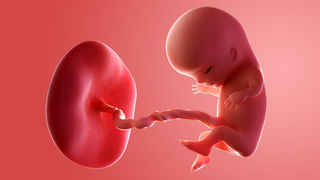

Your baby, or foetus, is now around 30mm long from head to bottom, which is about the size of a small apricot.

The baby will be making jerky movements and baby's movement can be seen on a scan.

Your baby is going through another huge growth spurt. The head is still too big for the body, but the face is more recognisably in proportion. The eyes are half closed but can react to light.

The ears are starting to form, the mouth now has a delicate upper lip and the nose has 2 little nostrils. The jaw bone is shaping up too, and contains tiny versions of your baby's milk teeth.

The heart is beating extremely quickly at 180bpm – that's about 3 times your heart rate.